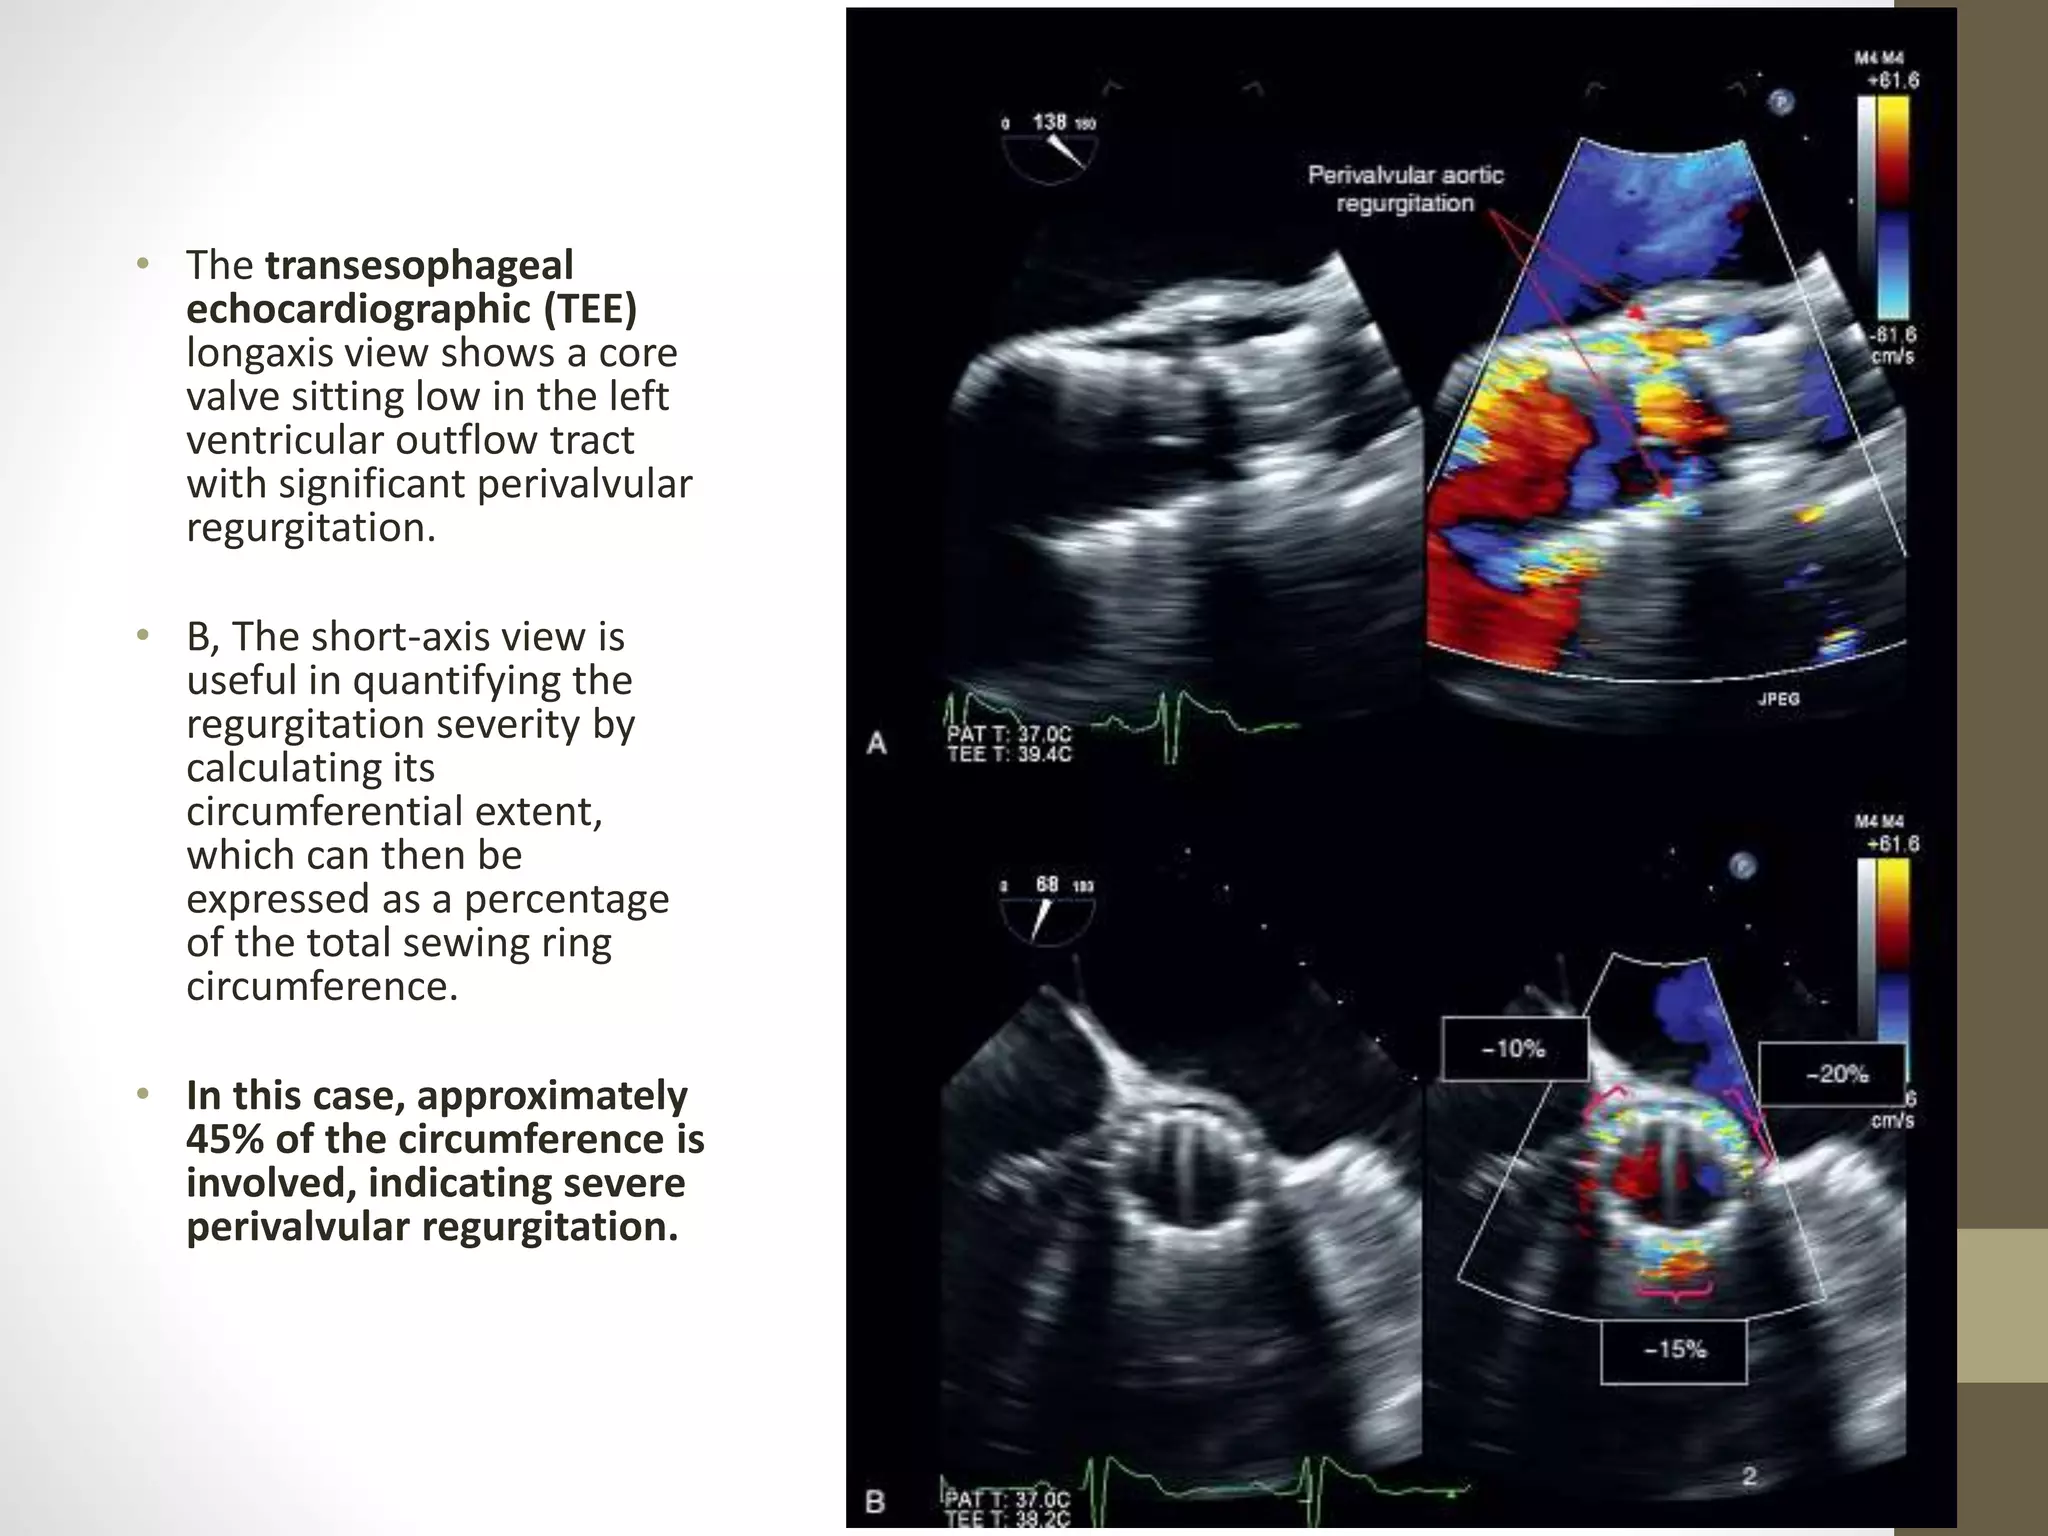

Pathologic Regurgitation

• The origin of regurgitation (valvular vs. perivalvular) is best assessed in the

parasternal short-axis view, where the full circumference of the annulus can be

visualized.

• The grading of perivalvular regurgitation is often technically difficult, as

regurgitant jets are frequently multiple, crescentic in shape, and wall hugging

within the LVOT.

• Careful interrogation of the neck of the jet just below the sewing ring is required

to accurately define its circumferential extent,

• which can then be expressed as a percentage of the total sewing ring

circumference and used to estimate severity (<10% ¼ mild; 10% to 20% ¼

moderate; >20% ¼ severe).

• This method can be used when assessing all types of prosthetic aortic valve,

including TAVI

• The transesophageal

echocardiographic (TEE)

longaxis view shows a core

valve sitting low in the left

ventricular outflow tract

with significant perivalvular

regurgitation.

• B, The short-axis view is

useful in quantifying the

regurgitation severity by

calculating its

circumferential extent,

which can then be

expressed as a percentage

of the total sewing ring

circumference.

• In this case, approximately

45% of the circumference is

involved, indicating severe

perivalvular regurgitation.